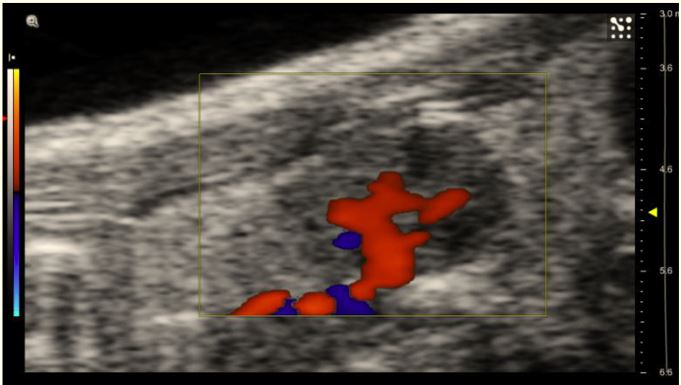

US and CEUS were used to identify and characterise ovarian glands in murine models as a preliminary study for exploring the protective role of gonadotropin-releasing hormone analogue (GnRH-a) on chemotherapy-induced ovarian damage.